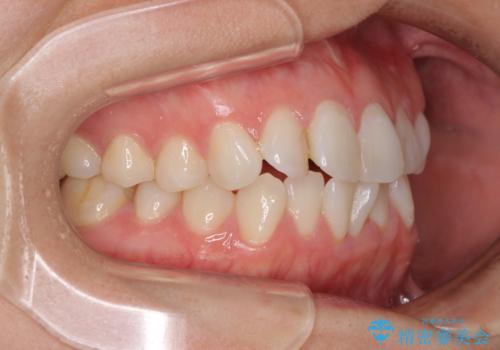

長年気にしていた前歯 インビザラインで目立たず改善

- ワイヤーではない矯正治療があると聞いたとのことで来院された患者様です。

長年前歯のデコボコを気にしていたもののワイヤー矯正に抵抗があり躊躇していたそうですが、インビザラインなら治療してみたいとのことで相談にいらっしゃいました。

インビザライン適用の歯列であったため、歯と歯の間を削るIPRを用いて改善することとしました。

下顎前歯の叢生が顕著な場合、歯列改善後に歯と歯と歯肉の間にブラックトライアングルという隙間ができてしまいます。

軽減することはできますが、完全に解決することは矯正治療のみでは不可能なため、リスクとして事前に周知しておく必要があります。